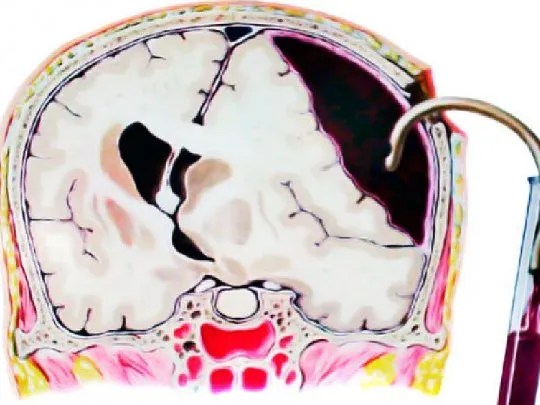

Para entender qué es un hematoma subdural, antes tenemos que saber que el cerebro está recubierto de una serie de capas que lo separan del mundo exterior. Es decir, no está el cerebro, el cráneo, el cuero cabelludo y el mundo, sino que hay varias capas entre estas que ya conocemos.

No quiero extenderme demasiado en esta parte, así escribiré otro artículo en el que explicaré estas capas más en detalle. Para esta ocasión, quiero que os fijéis bien en las Meninges.

Un HEMATOMA SUBDURAL (HSD) es la acumulación de sangre entre la Duramadre y la Aracnoides.

Se debe a la rotura de venas corticales en el espacio subdural, debajo de la Duramadre, cuando se dirigen hacia un seno venoso dural.

Si las venas se rompen en el espacio subdural, se acumula la sangre entre las dos meninges (Duramadre y Aracnoides) y se corta la conexión con el seno venoso dural correspondiente. Poco a poco, la sangre va ocupando un lugar que no le corresponde y esto aumenta la presión sobre el cerebro (hipertensión intracraneal). El cerebro se va «aplastando» poco a poco y se acaba produciendo daño cerebral.